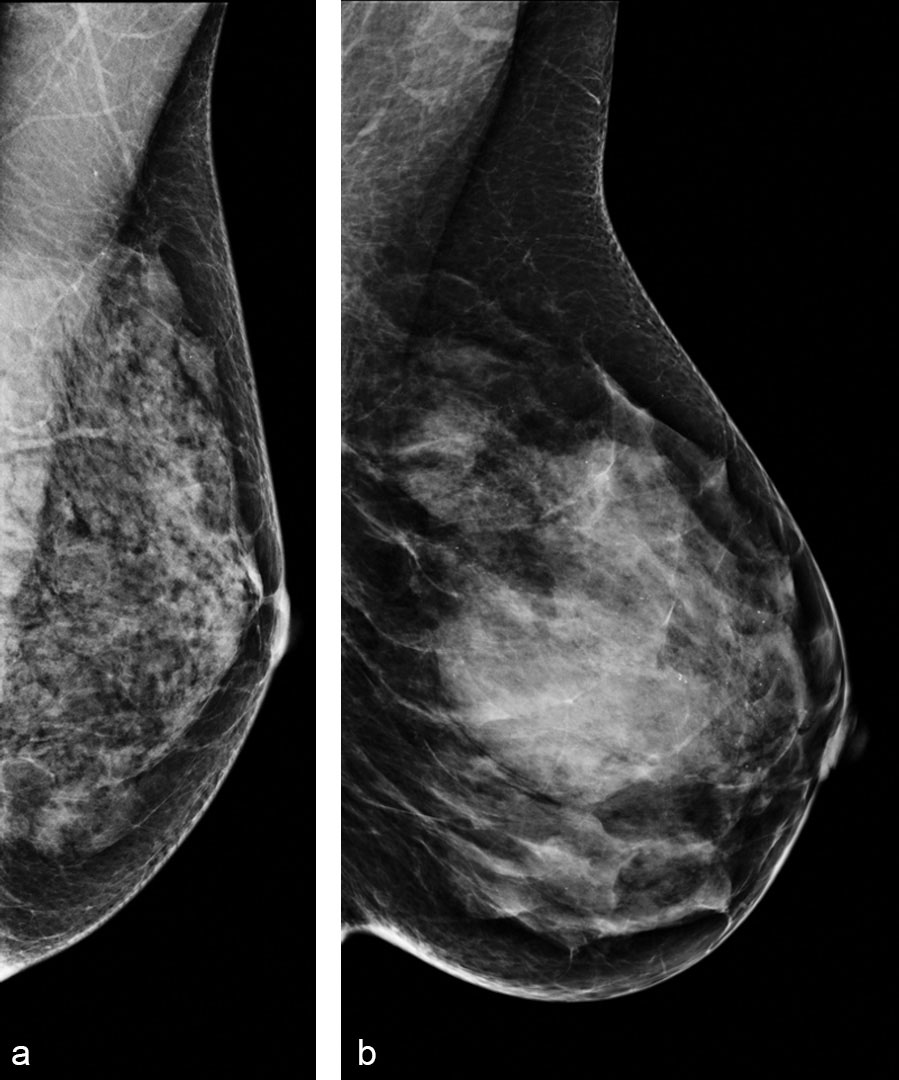

Lumps, both benign and cancerous, also appear white So, mammograms can be less accurate in women with dense breasts If a woman's mammogram shows she has heterogeneously dense or extremely dense breast tissue, sheIII The breast is heterogeneously dense This may lower the sensitivity of mammography IV The breast tissue is extremely dense, which could obscure a lesion in mammography Examples of these breast types are shown in Figure 1 Other pattern classifications include the sixcategory classification (SCC)There are four descriptors for breast density on mammography in the 5 th edition of BIRADS 1,2 a the breasts are almost entirely fatty b there are scattered areas of fibroglandular density c the breasts are heterogeneously dense, which may obscure small masses d the breasts are extremely dense, which lowers the sensitivity of mammography

a The breast are almost entirely fatty Mammography is highly sensitive in this setting b There are scattered areas of fibroglandular density The term density describes the degree of xray attenuation of breast tissue but not discrete mammographic findings c The breasts are heterogeneously dense, which may obscure small massesA few areas of dense tissue are scattered through the breasts (about 40% of women) The breasts are evenly dense throughout (about 40% of women) The breasts are extremely dense (about 10% of women) Women in the first two categories are said to have lowdensity, nondense, or fatty breasts Women in the second two categories are said to have highdensity or dense breasts About half of women who are 40 years old or older have dense Qualitative measures include the Wolfe grade (N 1, normal fatty breast;

Breast cancers are readily seen in fatty tissue with up to 98% sensitivity in film mammographyDense breast tissue itself is a risk factor for breast cancer, with the risk 46 fold higher in women Heterogeneously dense indicates that some areas of nondense tissue were found, but the majority of the breast tissue is dense About 40 percent women have this result Extremely dense indicates that nearly all the breast tissue is dense Breasts can be almost entirely fatty (A), have scattered areas of dense fibroglandular breast tissue (B), have many areas of glandular and connective tissue , or be extremely dense (D) Breasts are classified as "dense" if they fall in the heterogeneously dense or extremely dense (D) categories

Specialists term the breast tissue in type 3 as 'heterogeneously dense' The parenchyma ranges from 51% to 75% of the breast tissue 'Heterogeneous' means something contains many different items and has many different variations The Breast DensityBreast Cancer Connection In 1976, John Wolfe proposed a fourtiered classification of mammographic breast parenchymal patterns, after he had noticed a strong association between parenchymal pattern and breast cancer risk The more complex (and generally denser) the parenchyma, the higher the risk of subsequent breast cancerThe breast tissue is heterogeneously dense, which may obscure small masses (40% of women) The breast tissue is extremely dense This may lower the sensitivity of mammography (10% of women) Approximately 50% of women undergoing screening mammography are classified as having either "heterogeneously dense" or "extremely dense" breasts A letter is sent to all Spectrum Health